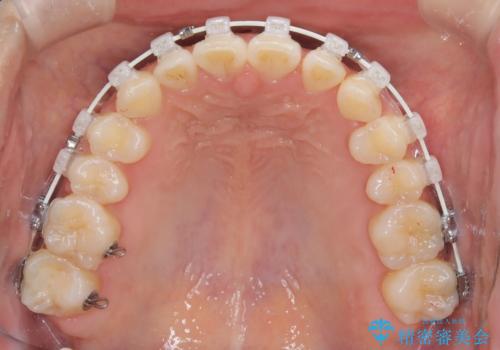

- 矯正装置

- 審美装置

最初は、一番後ろの奥歯でしか噛んでいない状態で、上下の前歯の先端がちょうど当たる切端咬合でした。

口腔習癖の改善及び、ワイヤー矯正にて歯列の平坦化を行うことで咬合を確立することができました。